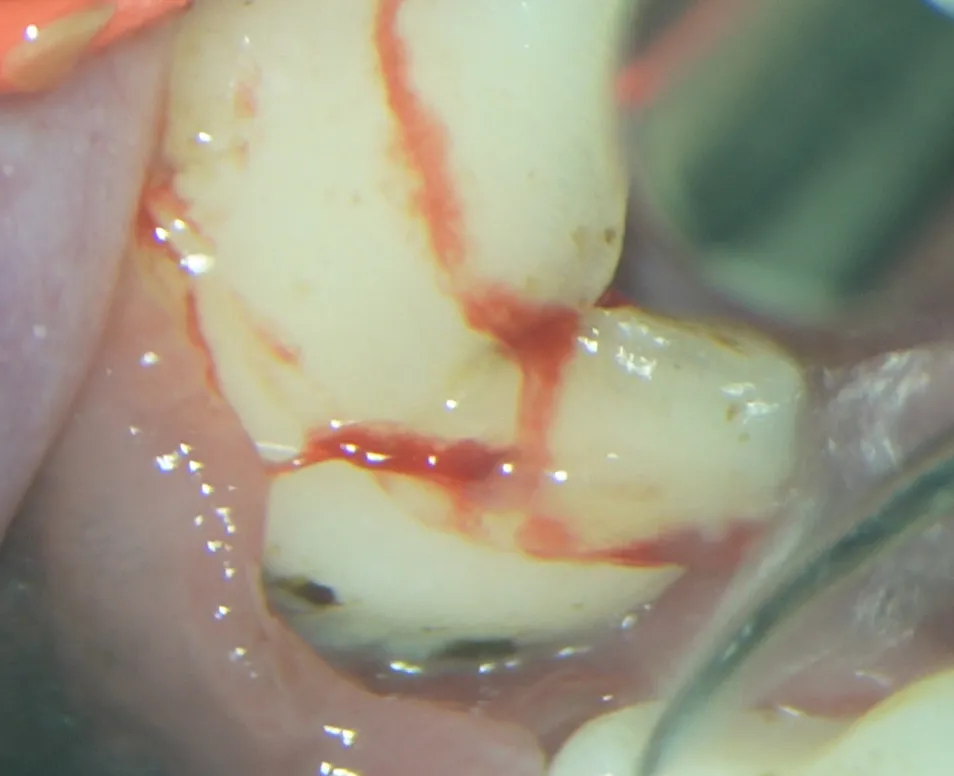

処置中(12.5倍)

暗くて見えにくい歯茎の下を拡大してみることにより以前よりプラークや歯石が見つけやすくなっています。歯周病が進行している箇所は、抜歯処置も行っています。